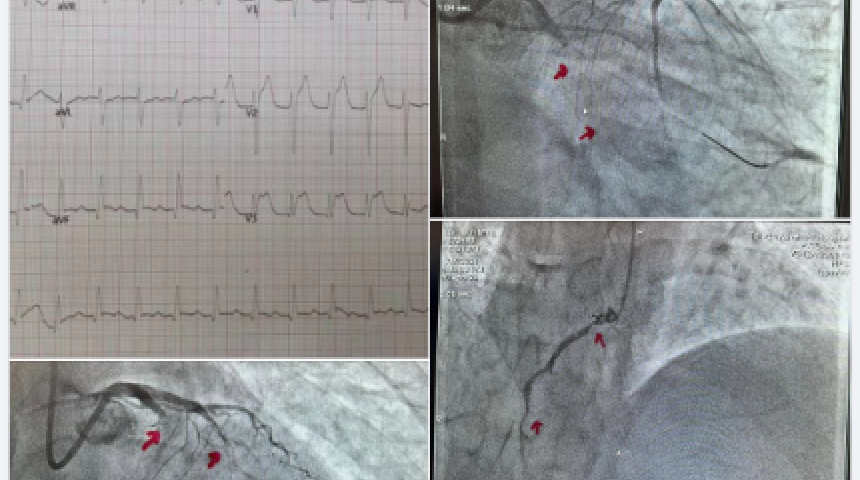

52歲老菸槍糖尿病胸痛檢查 驚現三條心臟血管全塞!